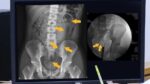

8旬翁大腿斷三截經三例手術,後來用髓內鋼釘固定已能站立。大甲李綜合提供 【Lai傳媒 記者爆料網